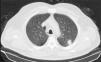

Presentamos el caso de un varón de 68 años, fumador de más de 40 paquetes/año, que es valorado en consulta de oftalmología por pérdida de visión en ojo derecho de 20 días de evolución. En la exploración ocular se detecta una trombosis venosa retiniana bilateral. Se amplía el estudio para descartar enfermedad sistémica secundaria. El estudio analítico, coagulación, serológico y autoinmune, junto con tomografía axial computarizada (TAC) cerebral, fue negativo. Se realiza radiografía de tórax detectándose un nódulo en lóbulo superior izquierdo (LSI). El TAC torácico confirma la existencia de una imagen nodular espiculada en la región posterior del LSI de 14mm compatible con neoplasia (fig. 1). El diagnóstico anatomopatológico fue congruente con adenocarcinoma pulmonar y el estudio por PET-TAC no demostró captaciones patológicas a otro nivel.